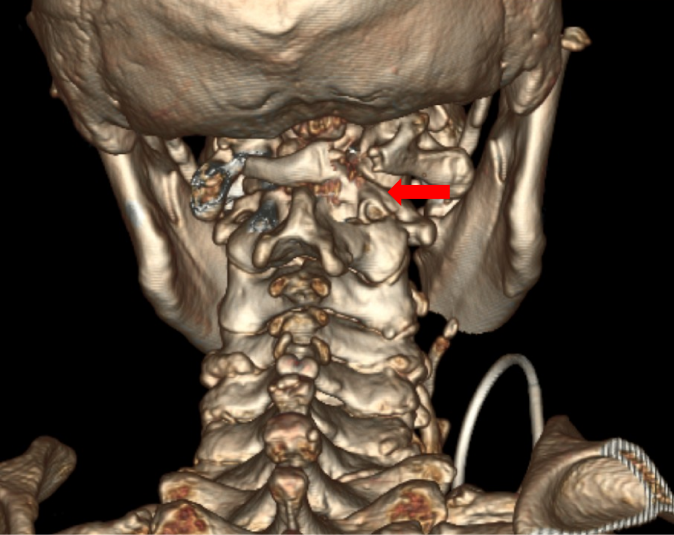

患者王先生已72岁,四肢乏力进行性加重10年,伴左下肢跛行4年,因担心需要手术治疗而没有正规就医。近期已无法独立行走,经推荐来到苏大附四院姜为民主任门诊就医。王先生的查体结果表现出明显的高位脊髓损伤症状:左上肢肌力下降至4级,左侧霍夫曼征、踝阵挛及巴彬斯基征均为阳性,左足下垂;右侧病情稍轻。影像学检查显示“游离齿状突畸形”——即第二颈椎(C2)齿状突发育异常并游离,后缘异常增生导致上段颈髓严重受压,脊髓功能受损使得患者近年来行走能力不断下降,并因此频繁跌倒,这对患者的生命安全构成了极大威胁。

图3:术后复查CT见骨性减压充分